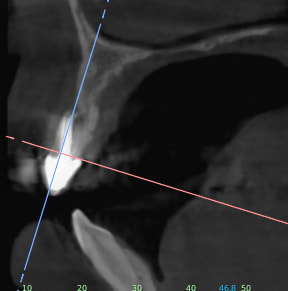

Je rajoutes quelques coupes et une rétro... C'est vraiment un massacre à la tronçonneuse!

24/04/2019 à 15h19

D'autres coupes et une rétro